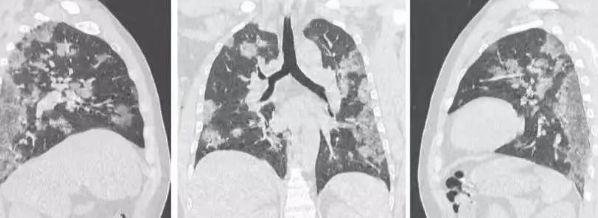

胸部CT还是核酸检测?

2月3日,身处疫情一线的武汉大学中南医院影像科副主任张笑春强烈推荐CT影像做为目前2019nCoV肺炎的主要依据。

因为核酸诊断试剂盒由于研究时间紧迫很难尽善尽美,生产流程复杂、满足不了大量的人群需求,加上核酸检测需要采样,受到方方面面的限制,会造成(假)阴性结果。

其实小编只想说,任何检测手段都有自身的优缺点,在核酸检测有疑议的情况下,辅助进行CT影像检测,或者如果在核酸检测条件不允许的情况下,用CT诊断作为补充手段进行查漏补缺,才是尽快确诊的良方。